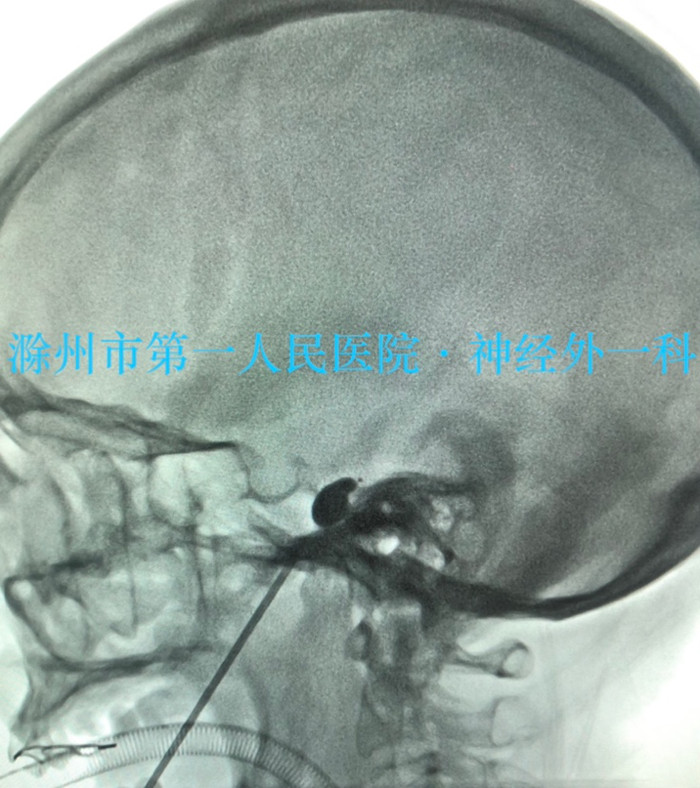

患者沈女士,56岁,先天性聋哑合并三叉神经痛。早期出现阵发性左下颌磨牙处刀割样疼痛症状时,患者考虑是牙痛引起的现象,多次在外院就诊治疗,在拔除疼痛相关区域的牙齿后症状仍得不到缓解,后就诊于我院神经内科,最终确定为三叉神经痛。为该患者完善术前评估后,主治医师多次与患者家属沟通,最终确定进行风险相对较小的“经皮三叉神经半月神经节球囊压迫术(PBC)”手术。手术从疼痛侧口角外侧(经典Hartel路径)用穿刺针进行穿刺,穿刺到位后通过穿刺针植入微球囊对三叉神经半月节进行压迫,仅仅2~3分钟即结束手术,手术顺利,术后患者恢复良好。